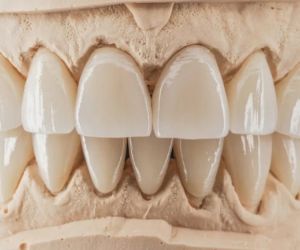

Виды зубных коронок

Зубная коронка – это наиболее известный вид реставрации зуба в стоматологии. Чтобы закрыть видимую часть естественной коронки зуба, и созда…

Коронки на передние зубы

Современная стоматология помогает не только полностью восстановить зубной ряд, но и решить вопросы, связанные с эстетикой улыбки пациента…